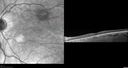

39 year old female She had no prior epsisodes of vision loss and then a week ago she noticed decreased vision in the right eye.  She has not had any health problems and she is not pregnant.  Phendimetrazine started 3 months ago.  She is not on steroids.   VA OD: sc20/63-1 NscJ16 VA OS: sc20/125-1 Dcc20/80 NscJ16 IOP: TP: OD:14 OS:14 Time:11:23 AM

Acute Bilateral Central Serous Chorioretinopathy - Female - Smokestack387 views39 year old female She had no prior epsisodes of vision loss and then a week ago she noticed decreased vision in the right eye. She has not had any health problems and she is not pregnant. Phendimetrazine started 3 months ago. She is not on steroids. VA OD: sc20/63-1 NscJ16 VA OS: sc20/125-1 Dcc20/80 NscJ16 IOP: TP: OD:14 OS:14 Time:11:23 AM00000